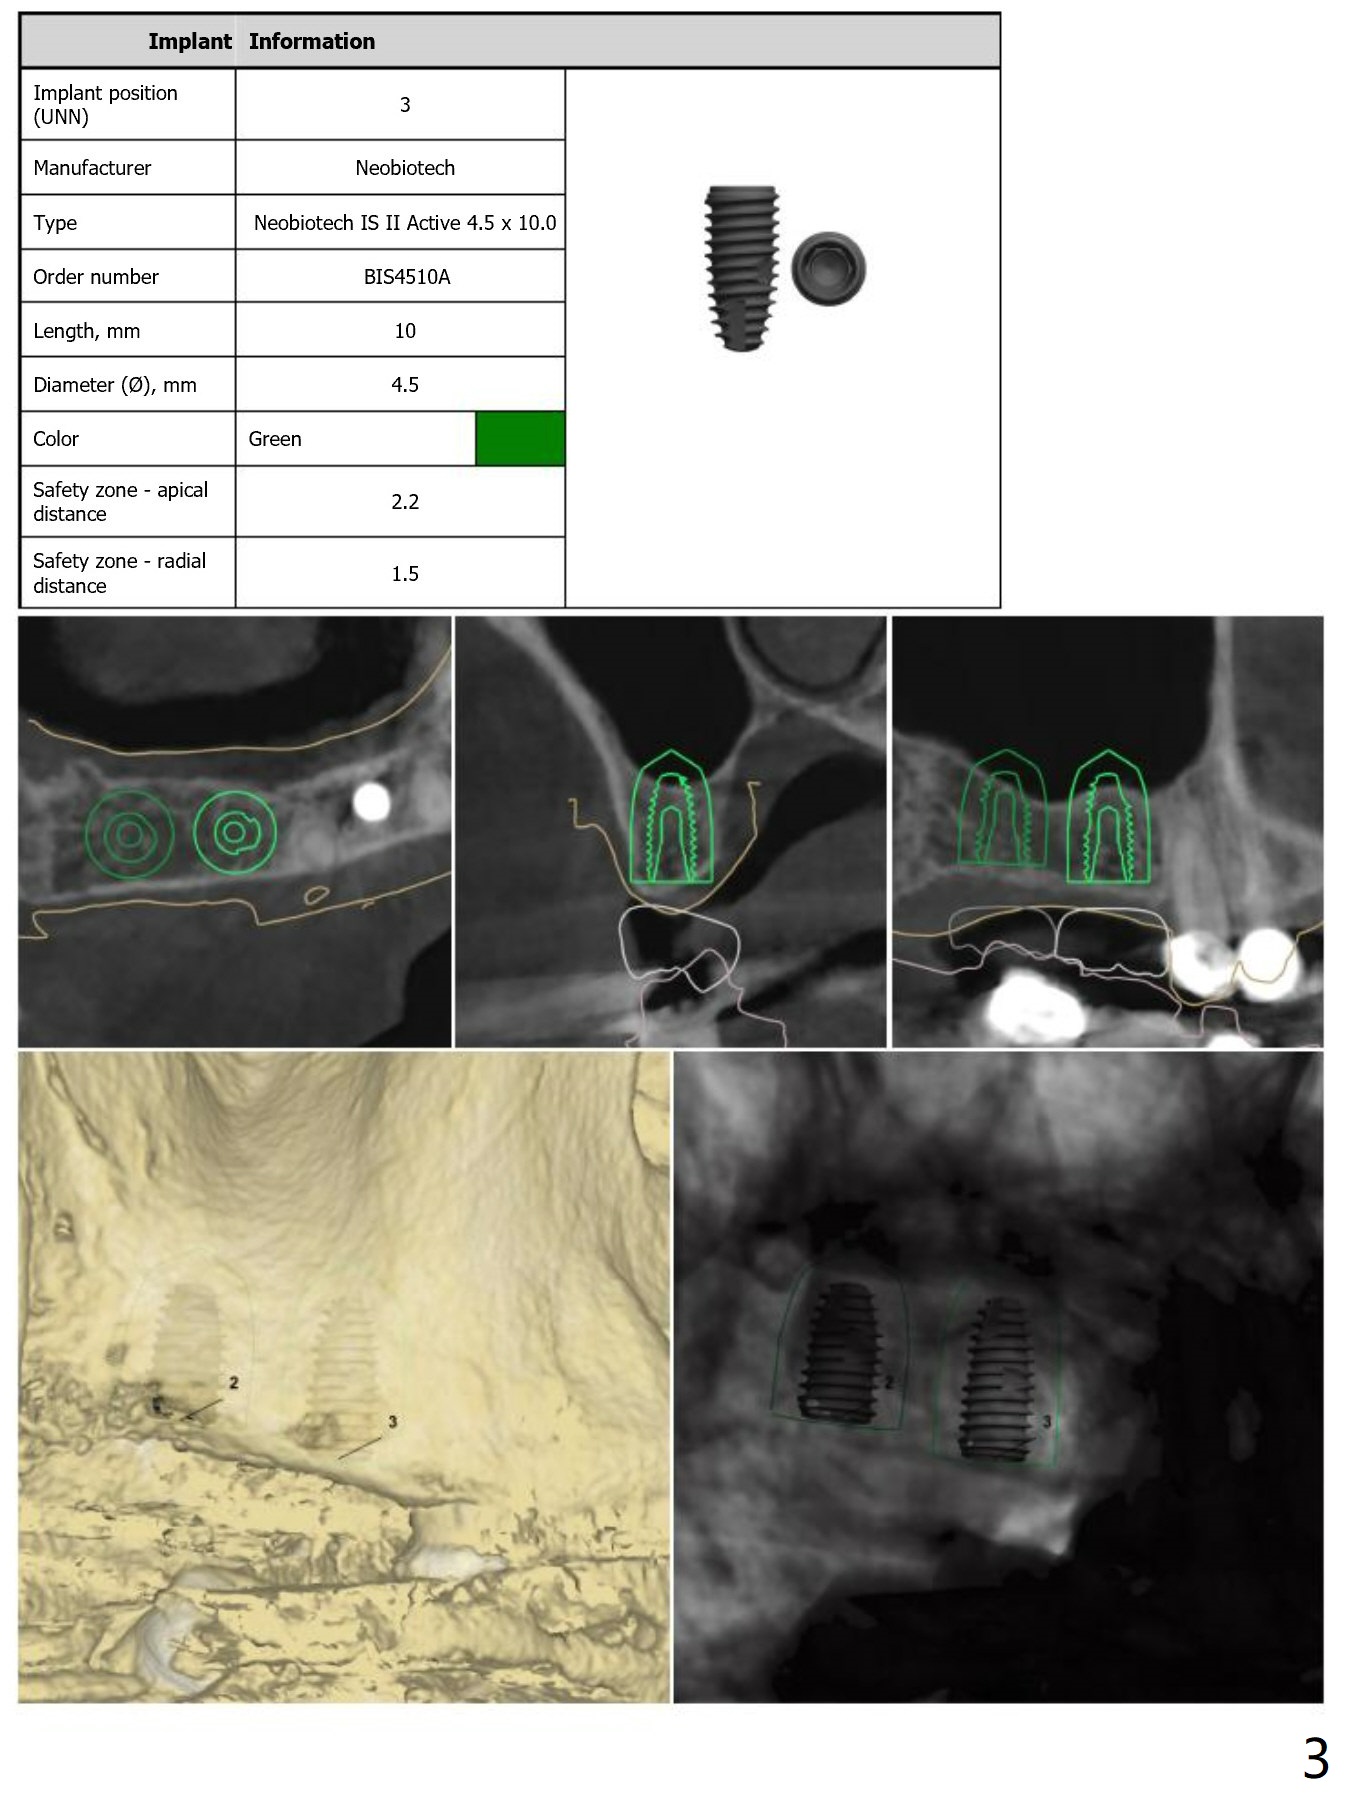

For short bone, Neo Navi drills are longer than they are supposed to be. Depth will be controlled by using O-rings. For example use an O-ring at the first mark as a stopper so that we do not have to take a good look while drilling (Fig.6,7). From that one, use 2 O-rings for the rest of way. As mentioned earlier, remove surgical guide for sinus lift (Sinus Master Kit). Replace the guide for implant placement. Note that tap drill is not needed, because of the soft bone in the posterior maxilla. Review Fig.1-5 for design, especially stopper for sinus lift at #2 and 3.